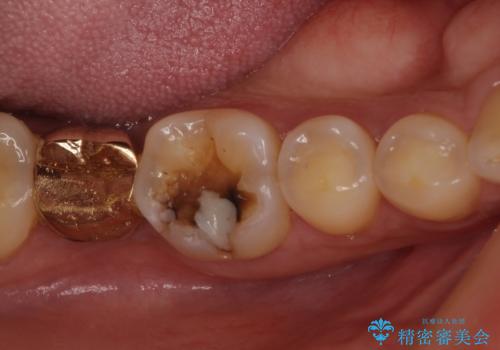

奥歯の深い虫歯をオールセラミックで治療